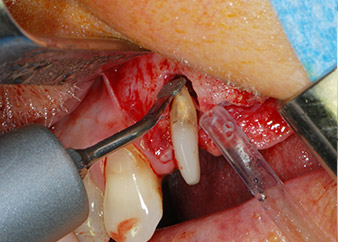

Nous avons toutefois maintenu notre projet initial de conservation des deux dents comme piliers temporaires d'un bridge pendant la période de six mois nécessaire à l'ostéointégration des implants. À la prochaine incision, la situation devrait être réétudiée. Premièrement, afin de gérer le problème endoparodontal, la surface de racine restante a été soigneusement débridée à l'aide d'un équipement piézoélectrique (Piezomed, W&H, utilisé avec l'insert en forme de spatule S1, initialement conçu pour limer la paroi sinusienne latérale) (Fig. 4).

débridement parodontal

Fig. 4 : Pour préserver la dent comme pilier temporaire, un débridement parodontal a été pratiqué à l'aide d'un équipement piézoélectrique...